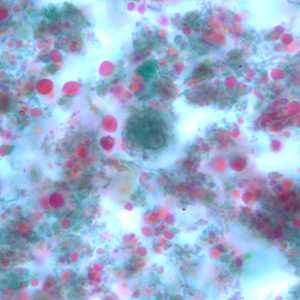

E. nana trophozoites stained with trichrome.

Figure A: Trophozoite of E. nana stained with trichrome.

Figure B: Trophozoites of E. nana stained with trichrome.

Figure C: Trophozoite of E. nana stained with trichrome.

Figure D: Trophozoite of E. nana stained with trichrome. Image courtesy of the Kansas Department of Health and Environment.

Figure E: Trophozoite of E. nana stained with trichrome.